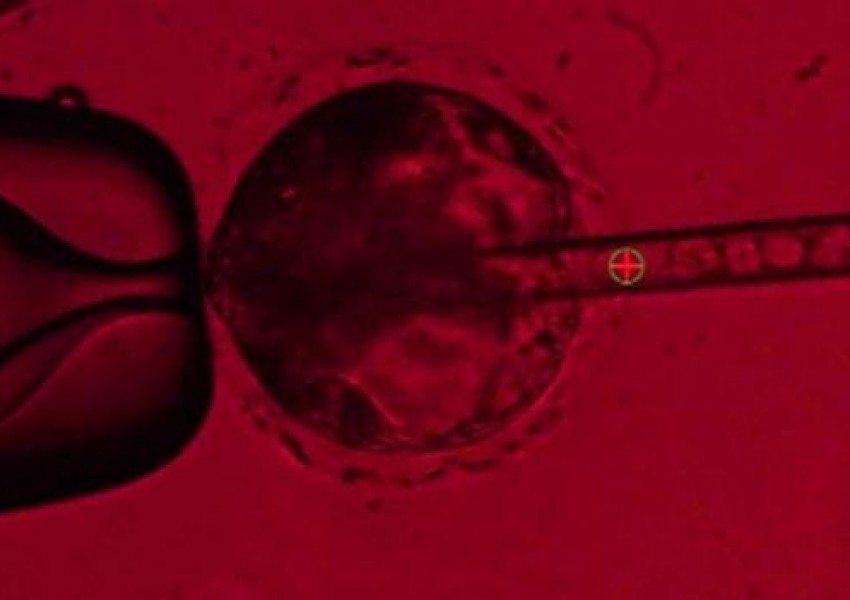

Учени "отглеждат" човешки органи в прасета

Американски учени се опитват да „отглеждат“ човешки органи в прасета. Те инжектирали човешки клетки в животинските ембриони, за да направят комбинирани тъкани между прасе и човек. Това проучването е част от изследване, целящо да намери отговор на...